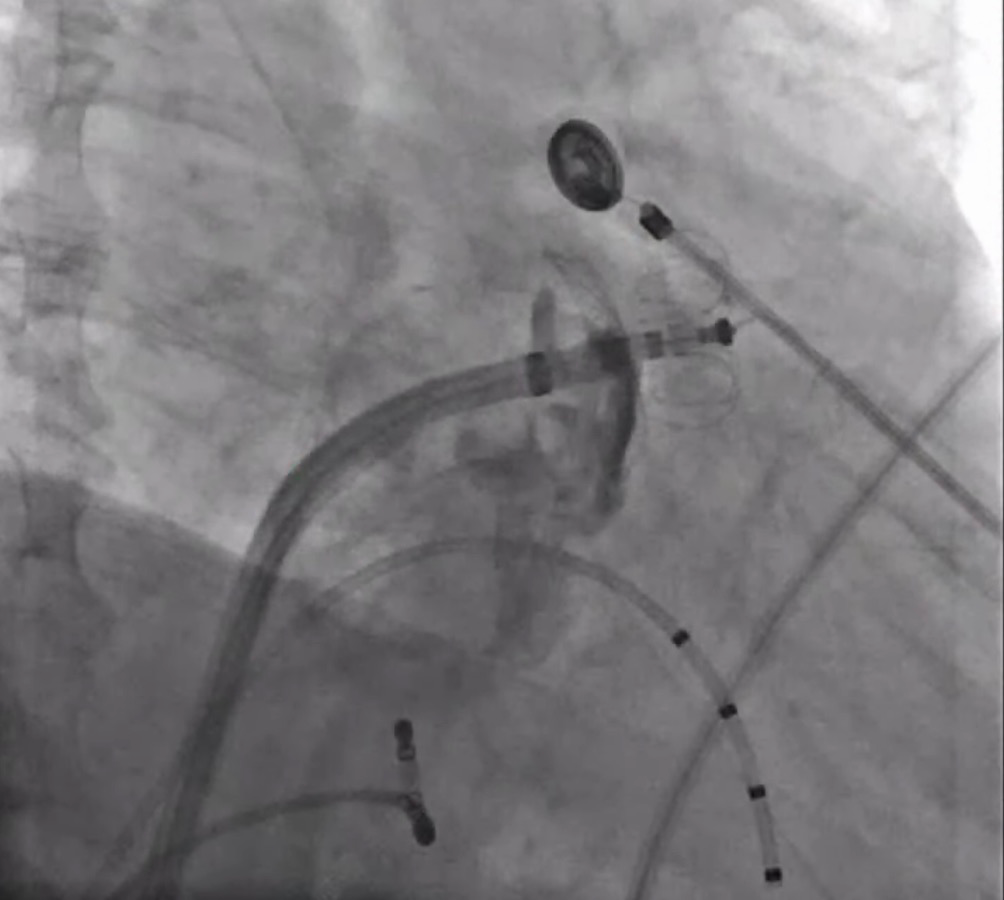

术中采用32mm规格CardioPulse™脉冲消融导管完成了4个肺静脉的电隔离,如图2为左下肺静脉与右上肺静脉消融DSA影像,肺静脉口内消融电极呈篮状,肺静脉口部及前庭部位消融电极呈花瓣状,消融后肺静脉电位消失,实现肺静脉完全隔离。

(a)左下肺静脉消融

(b)右上肺静脉消融

图2 采用CardioPulse™脉冲消融导管进行肺静脉消融

如图3所示,术中造影显示患者的左心耳固定区尺寸为23mm、深度25mm,选用规格为锚定盘直径26mm,密封盘直径 31 mm的左心耳消融封堵器植入到左心耳内。如图4-5所示,消融前后采用德诺电生理标测导管对左心耳进行电信号检测,对比结果表明左心耳电信号完全隔离;如图6所示,术者分别在左心耳消融前后进行了冠状动脉造影,造影显示回旋支无明显变化,无痉挛等不良事件发生;如图7-8所示,封堵器解脱前对左心耳消融封堵器进行了牵拉测试,器械无移位,造影及TEE超声显示左心耳完全封堵,无残余分流。

图3左心耳消融封堵器封堵至左心耳内